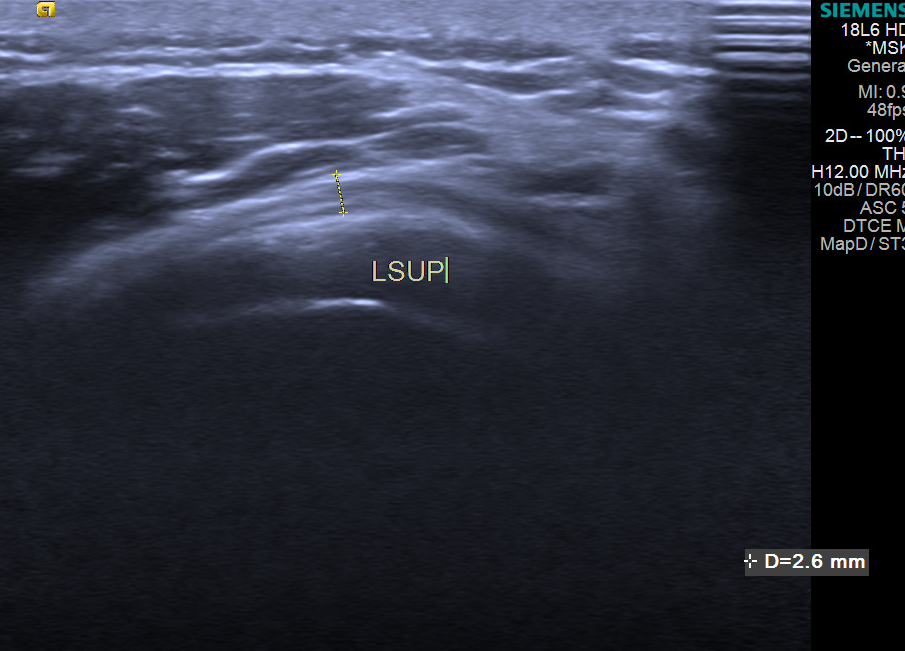

3.肩关节周围滑囊炎

诊断主要依靠测量肩峰下-三角肌下滑囊的厚度,其正常厚度应小于2mm,当滑囊厚度增加超过正常值时,结合临床症状及病史可初步诊断。